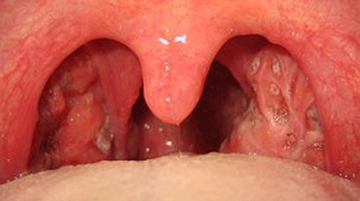

Bademciğe Ne İyi Gelir?Bademcikler, boğazın arka kısmında bulunan ve bağışıklık sisteminin bir parçası olan lenfatik dokulardır. Genellikle enfeksiyonlara karşı savunma mekanizması olarak görev yaparlar. Ancak zaman zaman bademciklerde iltihaplanma ve enfeksiyon görülebilmektedir. Bu durum bademcik iltihabı (tonsillit) olarak adlandırılır. Bademciğe iyi gelen bitkiler ve doğal yöntemler, bu rahatsızlığın tedavisinde yardımcı olabilir. Bademciği Rahatsız Eden BelirtilerBademcik iltihabının başlıca belirtileri şunlardır: